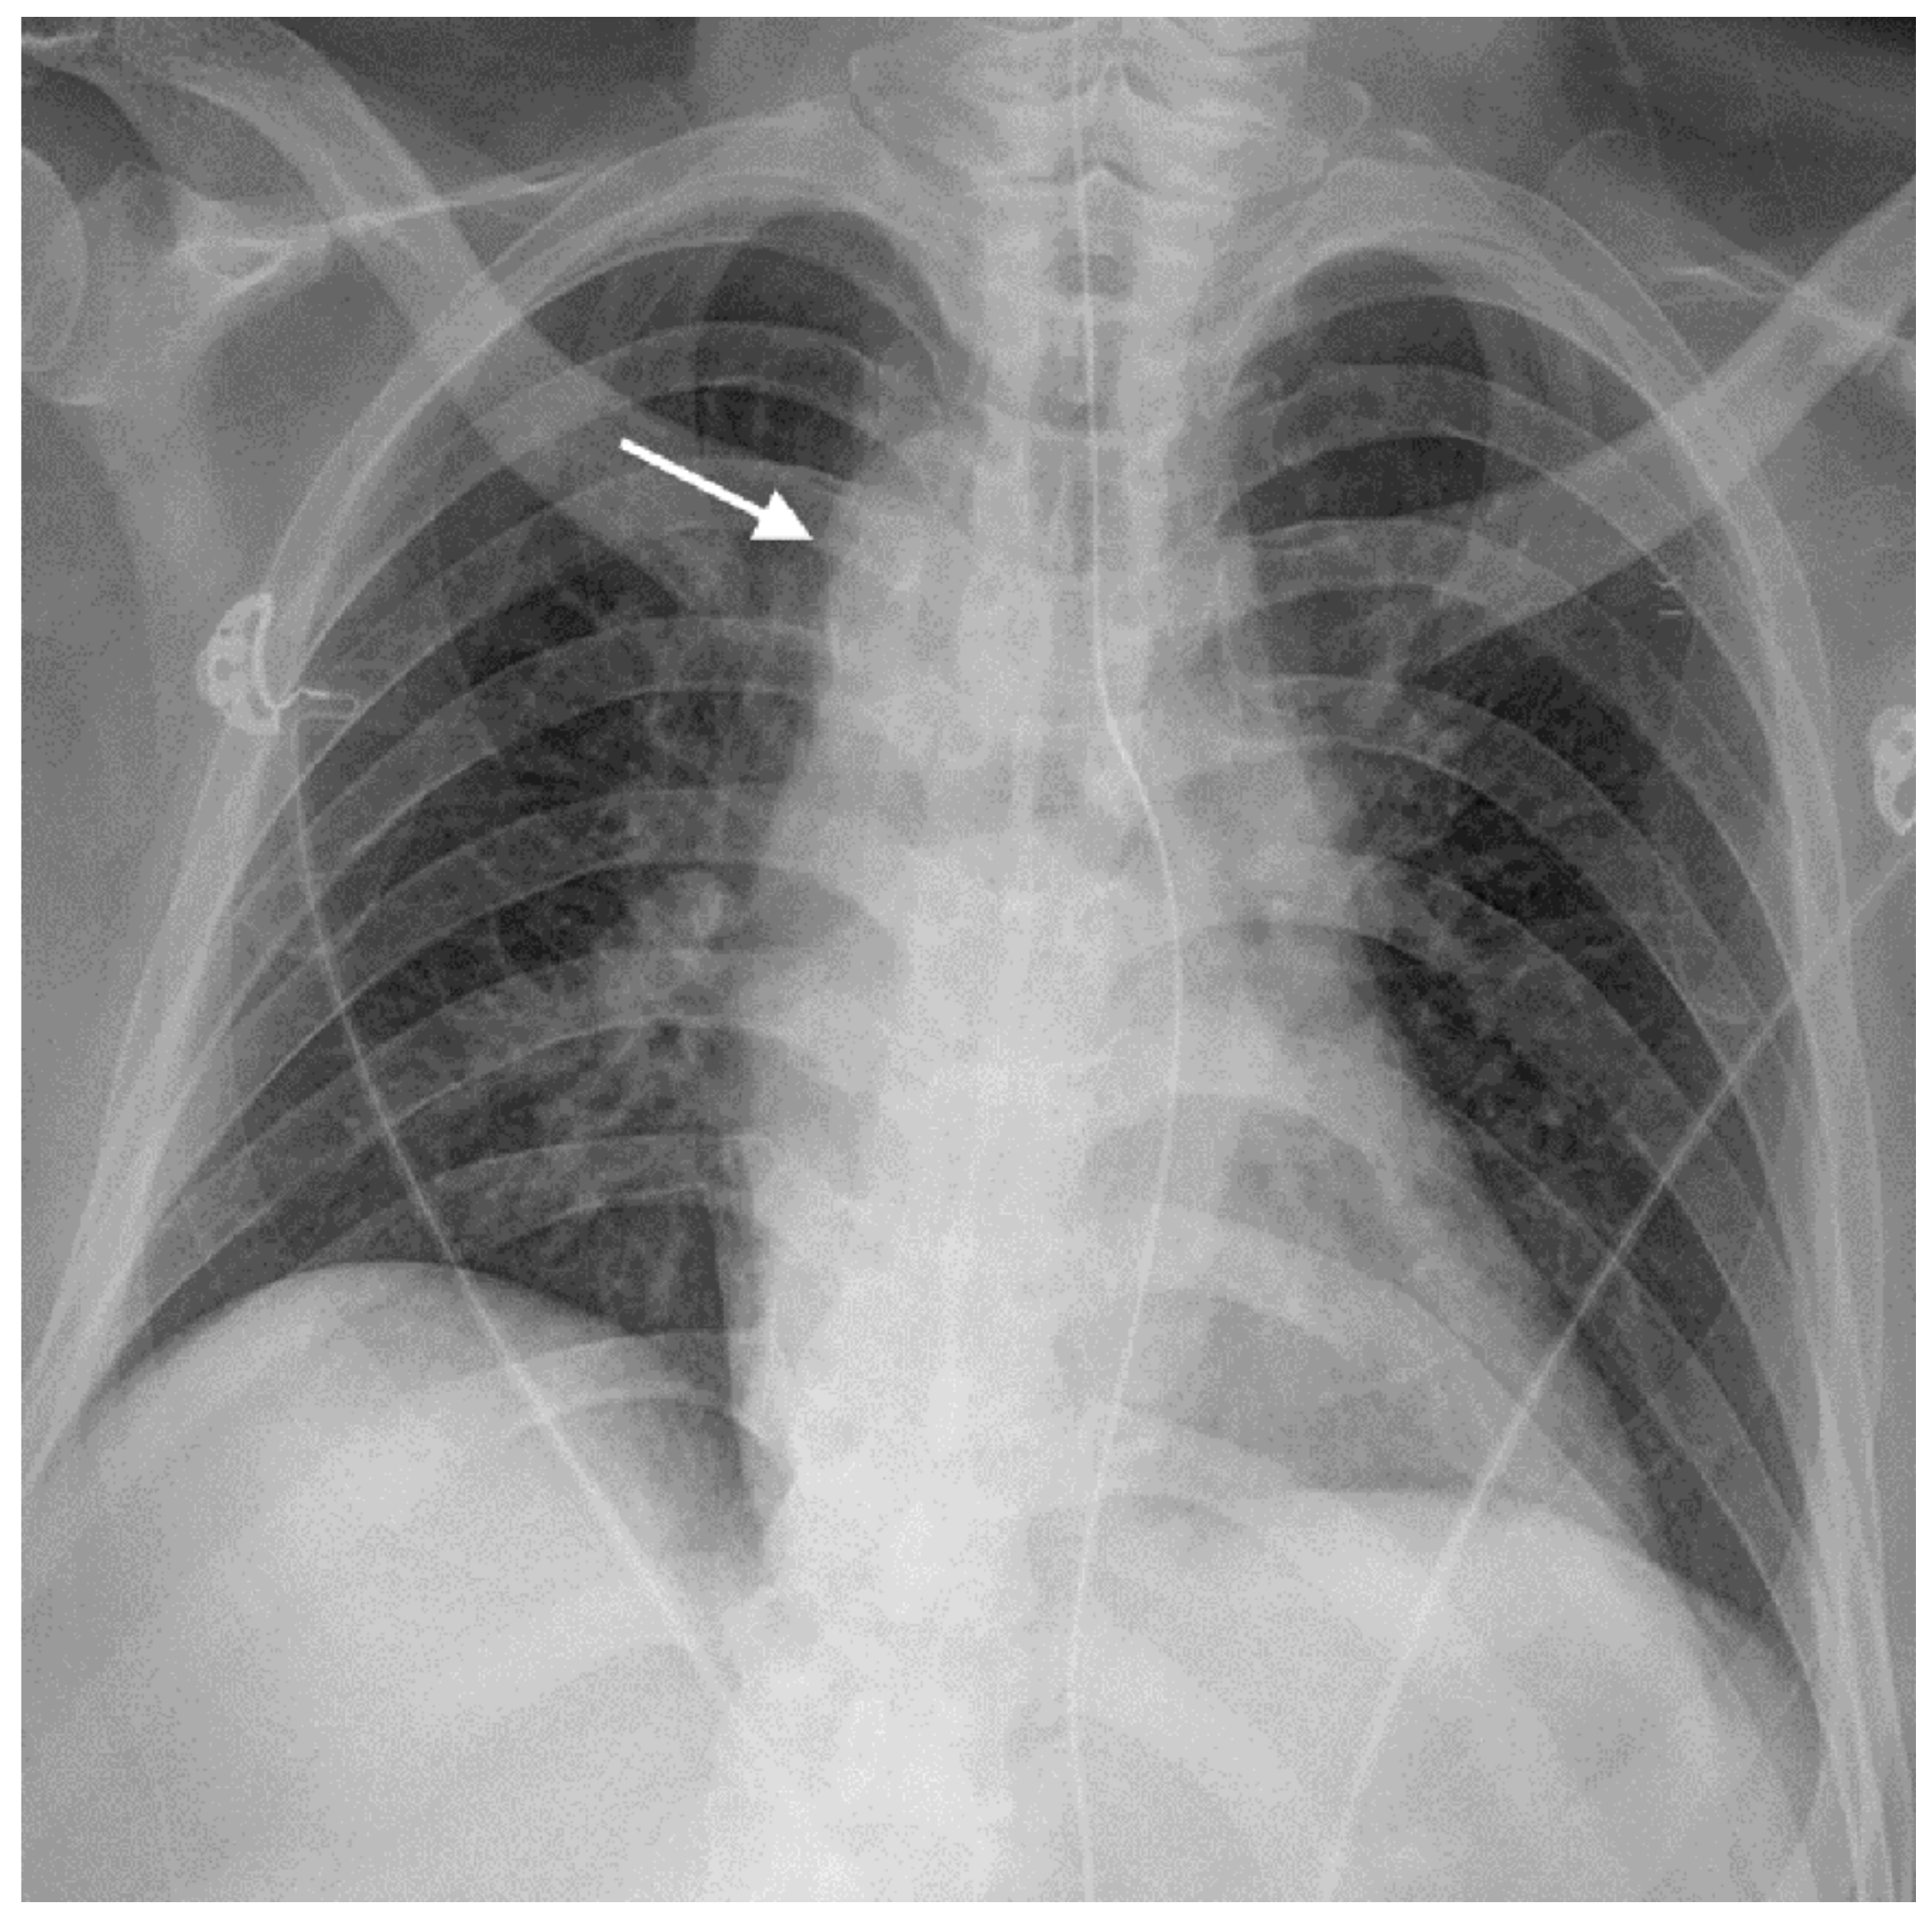

2. Case Report